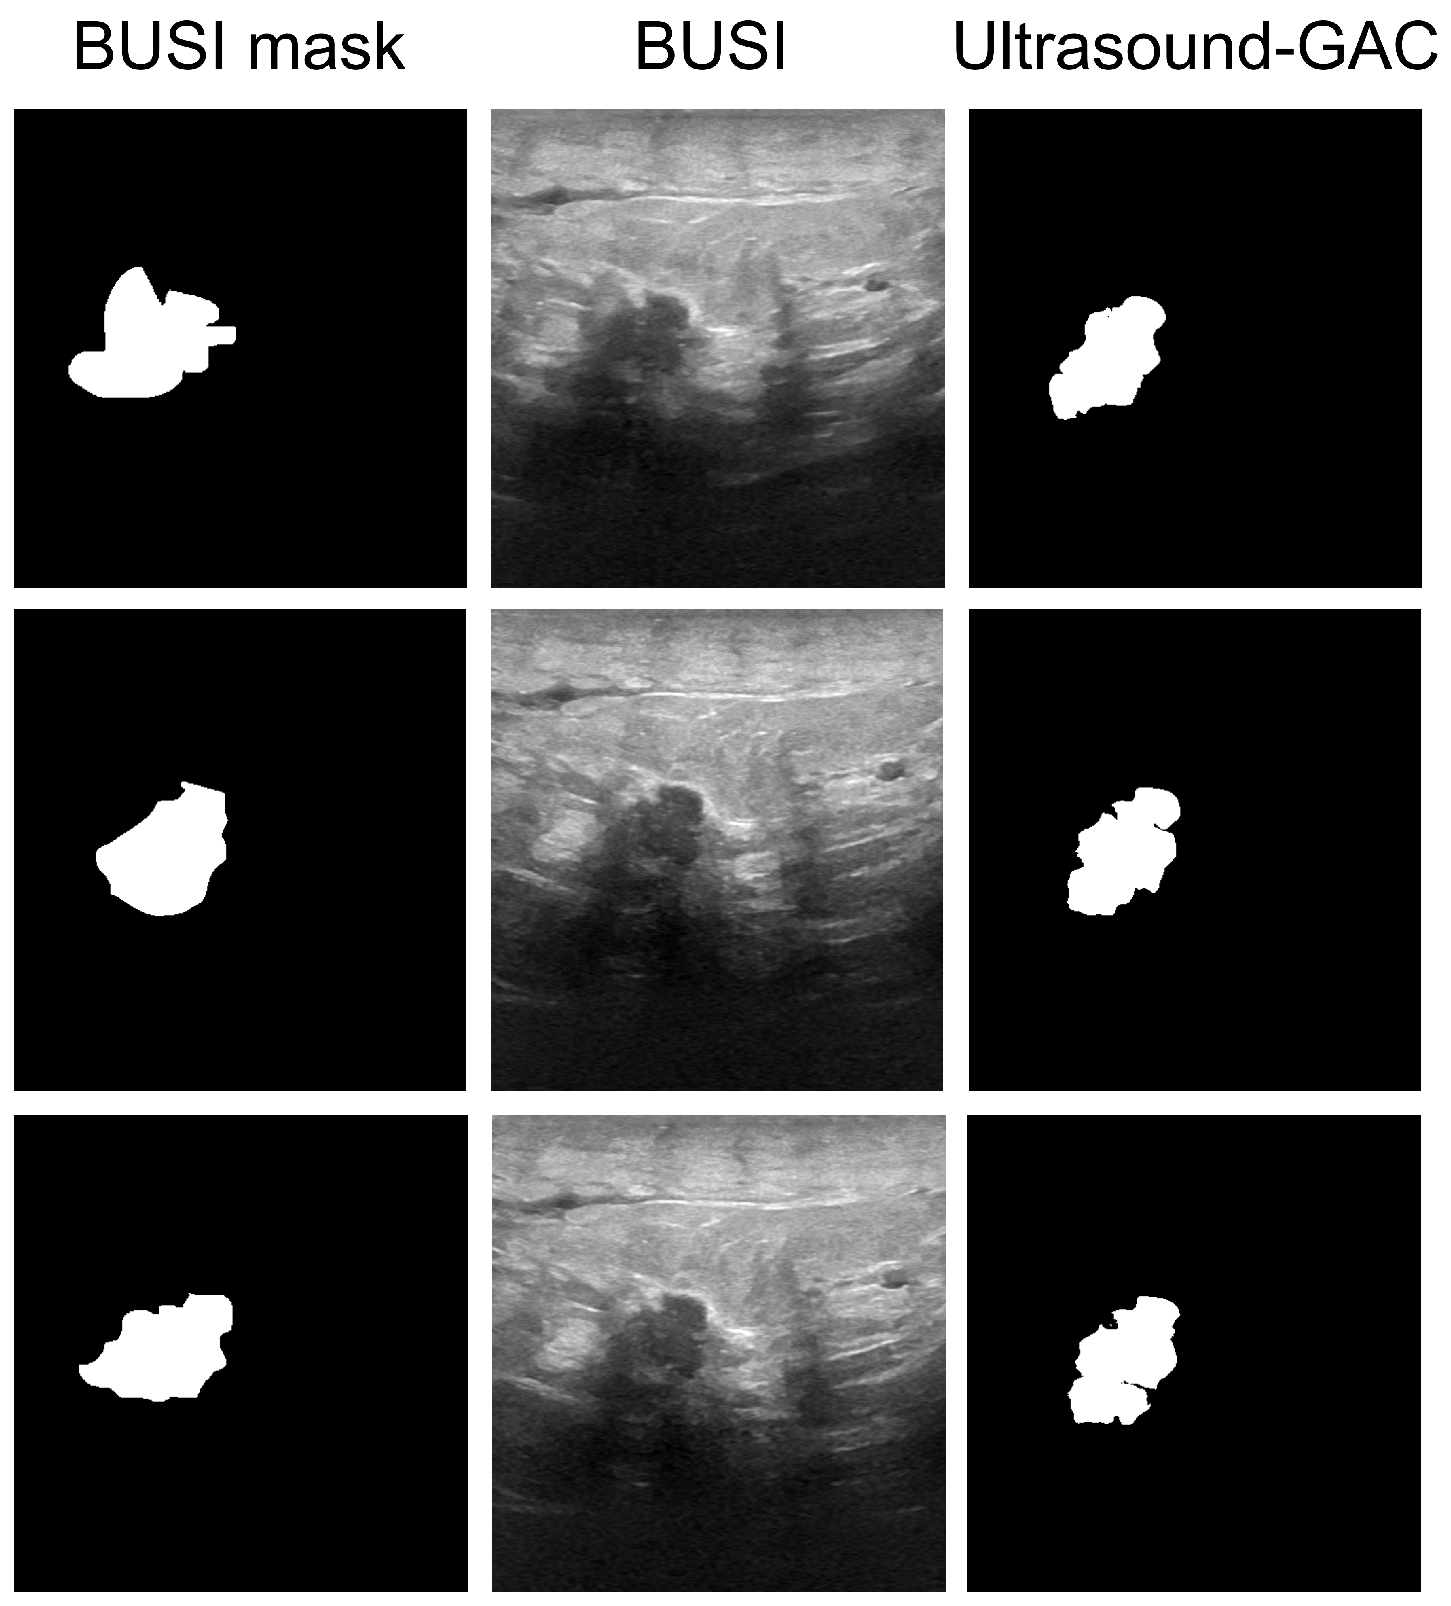

| Tumor Type | Median BUSI | Median MorphGAC | Mean ± Std BUSI | Mean ± Std MorphGAC | |

|---|---|---|---|---|---|

| Dice | Benign | 0.85 | 0.91 | 0.67 ± 0.36 | 0.70 ± 0.38 |

| Malignant | 0.58 | 0.70 | 0.53 ± 0.30 | 0.60 ± 0.32 | |

| all | 0.77 | 0.83 | 0.62 ± 0.35 | 0.67 ± 0.36 | |

| Center error [%] | Benign | 0.56 | 0.58 | 5.09 ± 11.23 | 4.22 ± 10.78 |

| Malignant | 4.13 | 3.27 | 7.21 ± 10.29 | 7.21 ± 10.65 | |

| all | 1.17 | 0.73 | 5.76 ± 10.95 | 5.14 ± 10.79 | |

| Area index [%] | Benign | 0.74 | 0.40 | 2.84 ± 5.21 | 2.11 ± 5.08 |

| Malignant | 9.25 | 4.34 | 11.64 ± 8.79 | 6.12 ± 6.49 | |

| all | 2.31 | 0.71 | 5.56 ± 7.67 | 3.35 ± 5.83 |